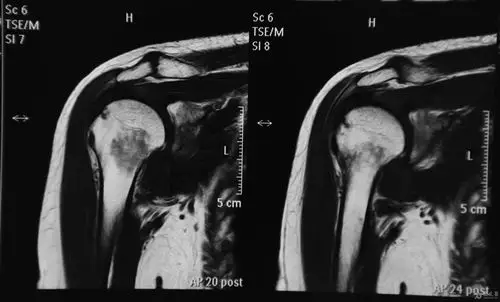

肩袖部分撕裂mri造影表现:韧带变细,其关节面缘见龛影形成,其诊断的